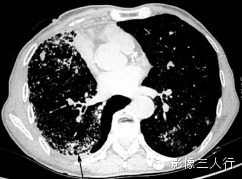

| 病毒性肺炎(图1) | 粟粒性肺结核(图2) | 细支气管肺泡癌(图3) | 肺尘埃沉着病(图4) | 肺泡蛋白沉着症(图5) | 血吸虫病(图6) | |

散在分布,6〜8mm或更小 | 分布均匀,直径1〜2mm | 分布不均,直径6〜7 mm | 分布不均,直径多为2〜5mm | 地图样、铺路石征 | 大小不等,直径多为1〜5mm |

较模糊 | 较清楚或较模糊 | 较清楚 | 较清楚 | 较清楚 | 较模糊 |

病灶密度相同,大小不等 | 病灶密度相同或不同 | 病灶密度相同,呈含气支气管征及蜂窝征 | 病灶密度不均,有钙化 | 磨玻璃密度,地图样分布和铺路石征 | 病灶密度不均,典型者可见晕征 |

无 | 无 | 可有 | 有,常见钙化 | 无 | 无 |

无 | 少见 | 较常见 | 可有 | 无 | 少见 |